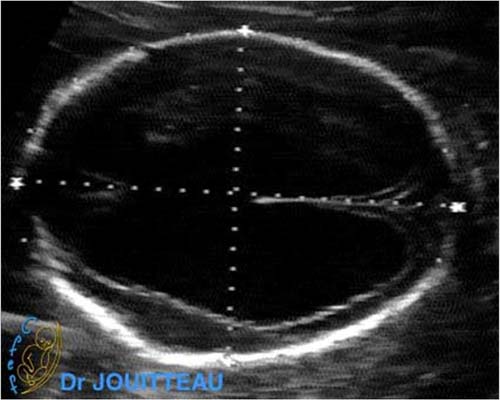

Selon la date de contamination, les lésions sont dues soit à une interférence dans l'organogenèse en cas d'infection précoce, soit à l'infection d'organes déjà formés. Les lésions cérébrales dépendent de la date de contamination du fœtus et, éventuellement, des réactivations successives. Le virus peut provoquer d'une part des lésions de nécrose focale par destruction cellulaire, suivie de lésions inflammatoires secondaires sous forme de granulomes à CMV, puis de sclérose. Pendant les quatre premières semaines surviennent des lésions de cytolyse, de vascularite et de ventriculite. Elles sont responsables de la constitution, au cours des semaines suivantes, de zones de nécrose et de sclérose, de thromboses et de nodules microgliaux. Il en résulte une destruction plus ou moins étendue du tissu cérébral avec atrophie, porencéphalie, gliose, calcifications parenchymateuses et, éventuellement, dilatation ventriculaire ou anomalies de migration et de gyration. La coexistence fréquente de lésions d'âge différent est un argument en faveur de réinfections successives (92).

La séméiologie échographique décrite par les différents auteurs comporte les signes suivants :